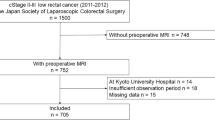

Patients

From July 2021 to July 2022, 120 patients with histopathologically verified rectal cancer underwent radical surgery. The inclusion criteria were as follows: (1) rectal carcinoma located ≤ 10 cm above the anal verge; (2) radical surgery scheduled within 2 weeks after rectal MRI (including 6–8 weeks after the completed neoadjuvant treatment); (3) patients with 1 ≤ LNs ≤ 15 on preoperative imaging findings. The exclusion criteria were as follows: (1) complete imaging and clinical data were unavailable.

Therapeutic regimen

Seventy-two patients underwent primary surgery without neoadjuvant therapy. Forty-eight patients received neoadjuvant chemoradiotherapy (neoCRT) and delayed surgery. Concurrent chemoradiotherapy regimen: concomitant radiation therapy (46 to 50.4 Gy/23 to 28 fractions, 5.5 to 6 weeks) and one to five cycles of simultaneous chemotherapy with capecitabine (865 mg/m2/bid).

From July 2021 to July 2022, a total of 120 cases were prospectively enrolled. Seventy-two patients did not receive neoadjuvant therapy, and forty-eight patients received neoadjuvant chemoradiotherapy. Table 1 summarizes and compares the basic demographic characteristics, tumor characteristics, and clinical features of the neoadjuvant therapy/primary surgery groups and categorizes the two cohorts according to the (y)pN status.

For evaluation on a node-by-node basis, only those LNs that could be identified were included. A total of 532 LNs were identified during imaging evaluation. Of these, 500 were confirmed on histopathological findings. Conversely, only 500/1377 (36%) nodes harvested from the mesorectum on histopathological examination could be matched to nodes on imaging evaluation (Fig. 2). Among the 500 matched nodes, 353 did not receive neoadjuvant therapy. A total of 147 received neoadjuvant therapy. The 500 matched LNs were randomly allocated to a training cohort and a validation cohort in a ratio of 7:3.